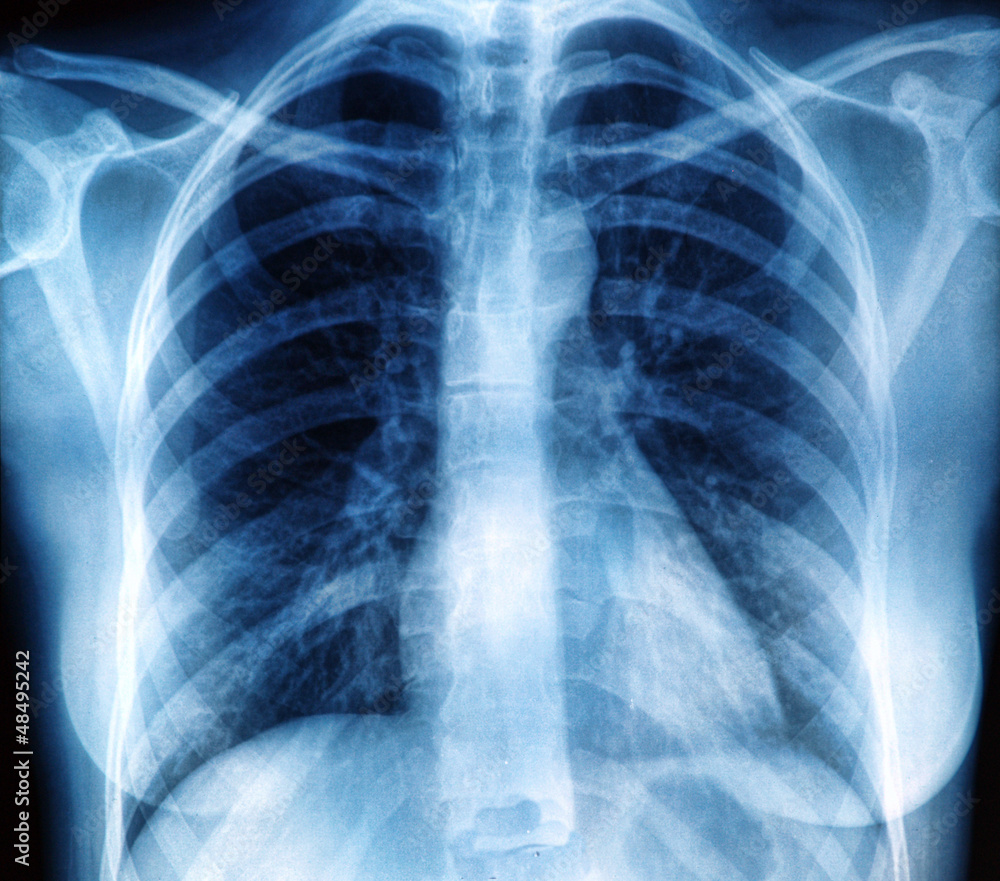

www.bigstockphoto.comChest X-ray Image In Blue Tone Stock Photo | Adobe Stock

www.bigstockphoto.comChest X-ray Image In Blue Tone Stock Photo | Adobe Stock

stock.adobe.comChest X-Ray | Cardiovascular Medical Group Of Southern California

stock.adobe.comChest X-Ray | Cardiovascular Medical Group Of Southern California